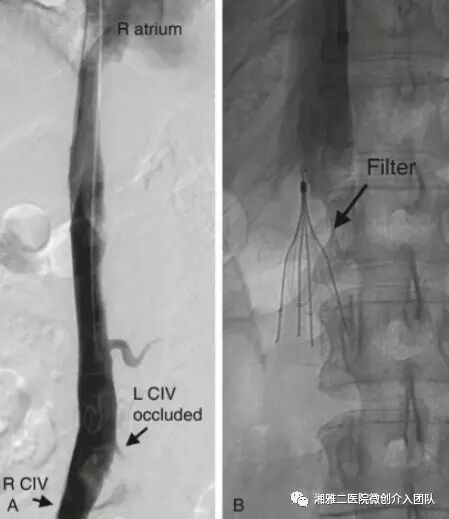

上图表示下腔静脉造影,左侧髂总静脉未见对比剂返流,提示左侧髂总静脉血栓,右图为肾静脉下滤器植入术后